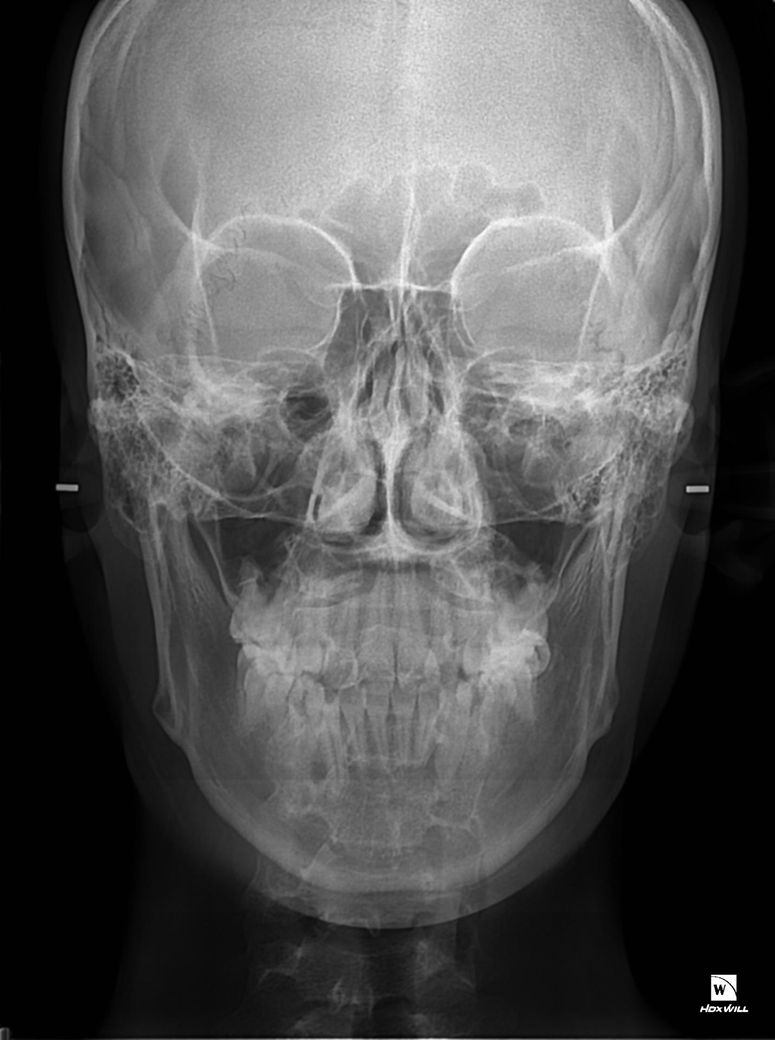

왼쪽사진이 악궁확장돌리기전이고 오른쪽사진이 악궁확장 돌리기후인데 왼쪽사진 엑스라이상에 광대뼈가 하얀색 이어로드에 닿지않고 공간이 널널한반면에 두번째사진에서는 하얀색이어로드 위치를보시면 광대뼈가 닿아있습니다 저만큼 광대뼈가 자랐다는건가요?

• 1번 째 사진